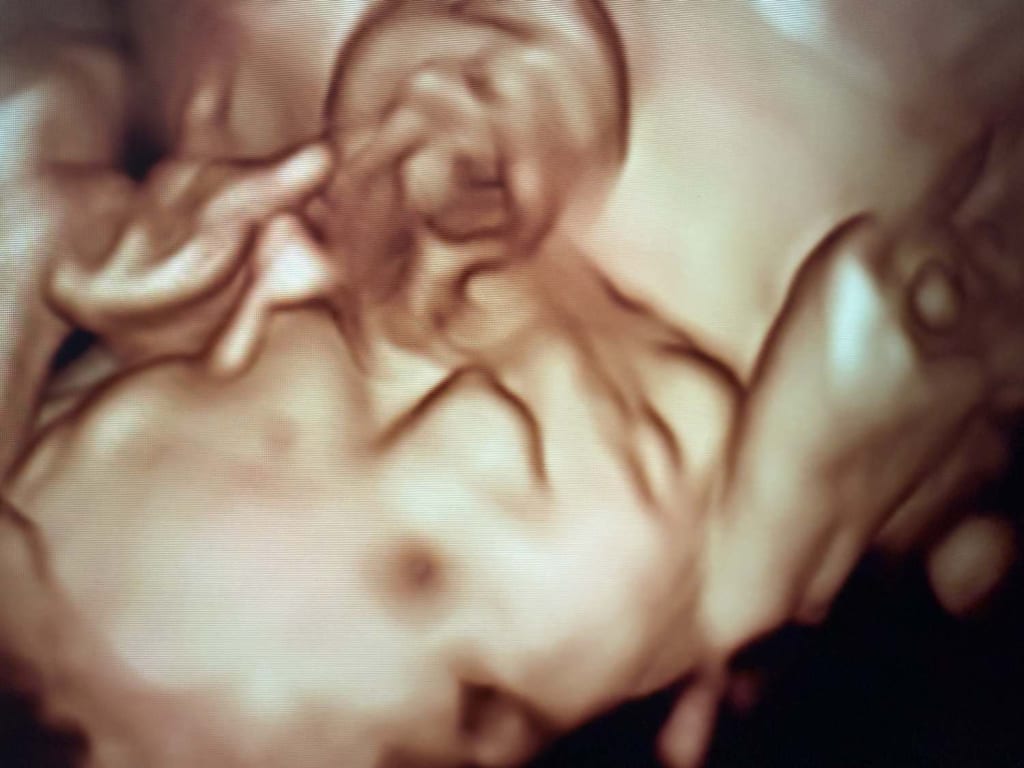

High-definition ultrasounds bring out the finest details of your baby's face and body, offering clarity that traditional 2D ultrasounds can’t match. For those in search of a truly special keepsake, a 4D ultrasound gender reveal in Philadelphia is an unforgettable experience. These scans allow you to not only learn your baby’s gender but also witness moments like a yawn, a smile, or a tiny stretch—moments that feel like a sneak peek into your baby’s personality.

4D ultrasounds have grown in popularity, not just for their emotional impact, but also because they provide additional diagnostic benefits. For example, seeing a baby’s movements in real time can help assess muscle tone, motor development, and other health indicators.